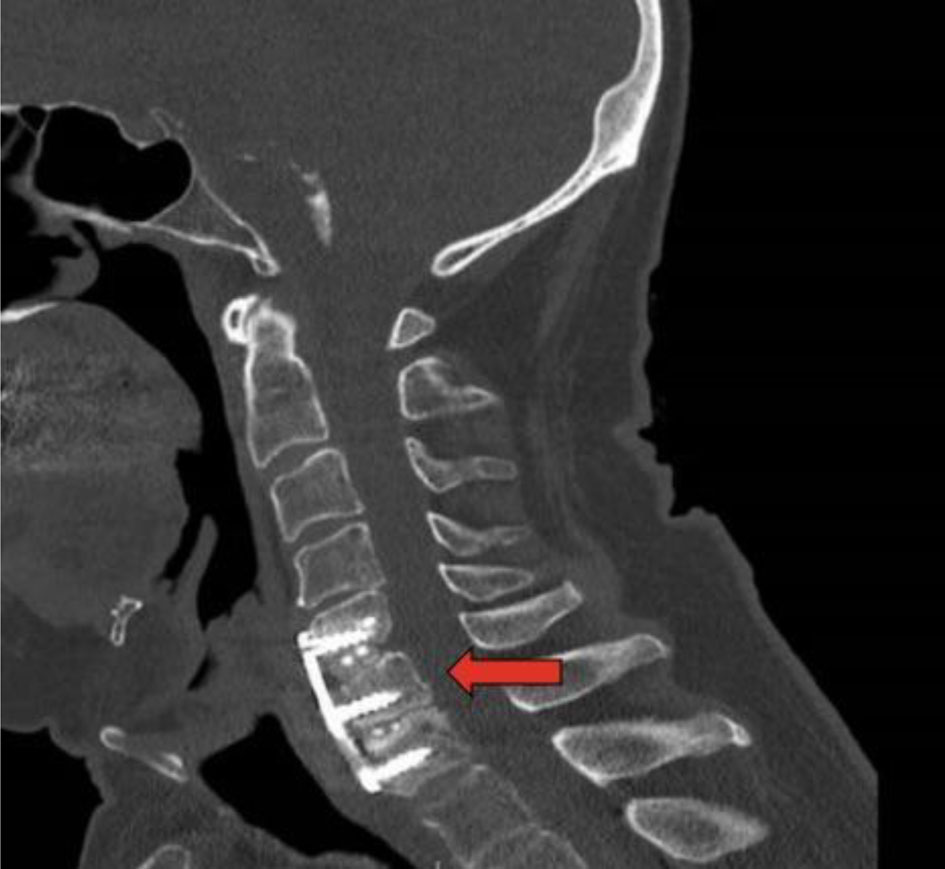

A 76-year-old man underwent C5-C7 ACDF in October 2017. Postoperative follow-up and examination included CT and esophagogram, which were negative for signs of acute complications. The postoperative recovery was uneventful and the patient denied any persistent neurological symptoms or symptoms of infection. At 6 months post-procedure, he developed vague dysphagia and weight loss of unknown etiology. A CT of cervical spine was obtained 6 months postoperatively and was negative for perforation (Fig. 1). X-rays of the cervical spine on flexion and extension at 6 months showed appropriate placement of the anterior plate and screws at C5, C6, and C7 with no motion across the fused levels. CT of the neck at 6 months postoperatively demonstrated mild residual multilevel foraminal narrowing with appropriate placement of the hardware and satisfactory surgical fusion from C5-C7 with no significant canal stenosis. Nevertheless, the patient reported dysphagia and continued weight loss regardless of the battery of inconclusive procedures and scans he underwent at multiple institutions.

![]() Click for large image | Figure 1. Computed tomography of cervical spine 6 months postoperatively. Red arrow indicates cervical plate. |